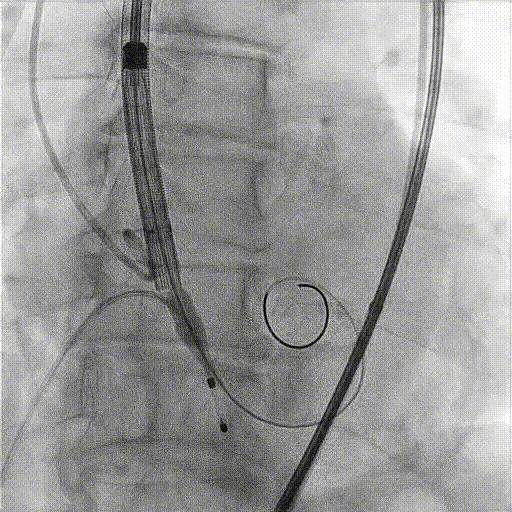

PCI植入过程:

术中影像:

Quantum 球囊扩张

复查冠脉造影血流通畅